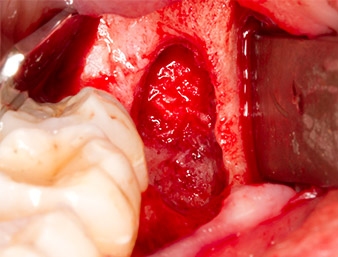

Periapical inflamed tissue was also removed very carefully with a manual excavator. Fig. 12 shows the empty alveole with exposed inferior alveolar nerve.

inferior alveolar nerve

Fig. 12: The inferior alveolar nerve can be seen in the bottom of the alveole.